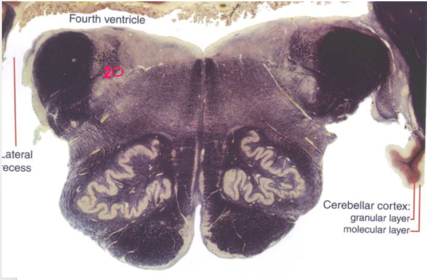

| Superior cerebellar peduncle | |

| Dentate nucleus | |

| Fastigial nucleus | |

| Anterior spinocerebellar tract | |

| Middle cerebellar peduncle | |

| Superior vestibular nucleus | |

| Medial lemniscus | |